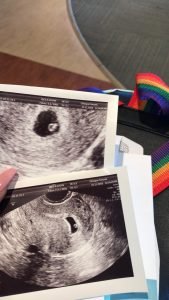

“La première échographie a été faite vendredi dernier. Merci à notre surrogate de notre avoir fait partager ce moment inoubliable.“

“The first ultrasound was done last Friday. Thank you to our surrogate for sharing this unforgettable moment.“